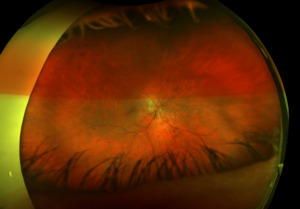

Posterior segment revealed IOL implants that were clear and centered after YAG Capsulotomy in both eyes. The optic nerve heads were both crowded with cupping of 0.10/0.10 (H/V) OU. The neuroretinal rim was intact in the right eye with no evidence of hemes, pallor, edema, or neovascularization of the disc. When observing the left eye, an inferior and inferior temporal rim hemorrhage was noted. Clinically, there was no apparent edema. There was a questionable area of swelling inferior temporal and superior temporal, but it was difficult to view. The vessels surrounding the optic nerve did not appear to be obscured and no spontaneous venous pulse was noted. The macular area was flat with even pigment and no clinically significant macular edema was present in either eye. Vessels displayed a normal AV ratio. The peripheral exam noted no holes, breaks, or tears in either eye. Finally, giant cell arteritis (GCA) symptoms of were ruled out.

After additional testing was completed, and comparison of previous photos were conducted, it was determined that the patient had not only optic disc drusen, but also possible bilateral amiodarone optic neuropathy. The photos 4 months apart shows increasing pallor in the left eye and a blood vessel at 7 o’clock that did not look obscured initially but was evidently more pronounced on the follow up when comparing the initial and follow-up photos. This shows the importance of quality serial fundus photography.

Right image is original exam with inferior hemorrhage. Left image is 4-month follow-up visit. Resolution of the hemorrhage is seen, but atrophy of the disc overall should be noted. Vessel at 7 o’clock should also be noted. It appears much more pronounced than on initial visit.